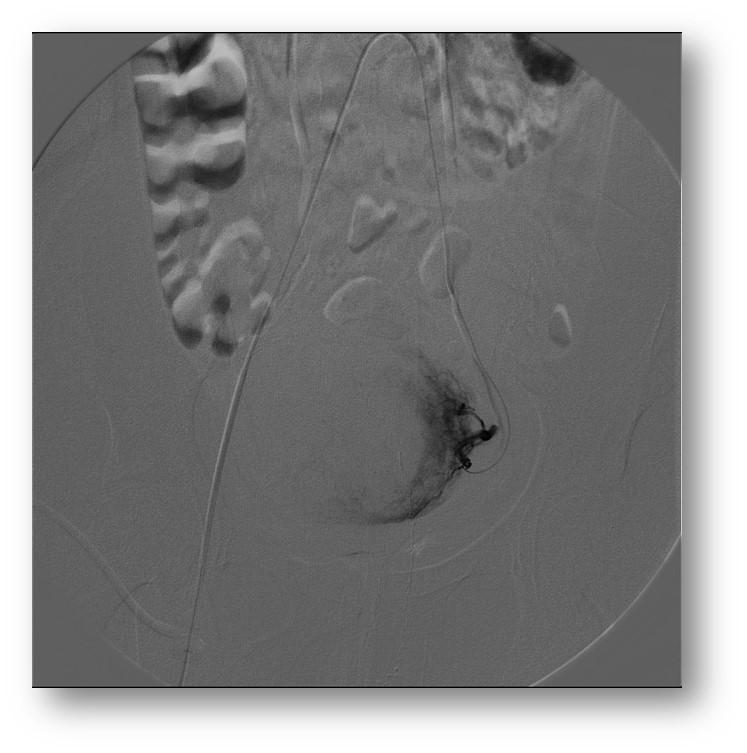

Como é feita e embolização dos miomas uterinos?

A embolização é um procedimento minimamente invasivo que consiste em uma

punção na região da virilha seguido de inserção de um fino catéter que vai até

a região dos miomas. Através deste catéter são injetadas partículas que são

pequenas bolinhas que ocluem a irrigação de sangue para os miomas. Assim os

miomas regridem e deixam de causar sintomas.